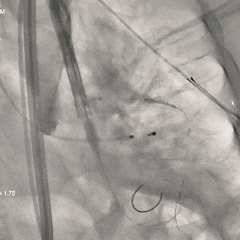

瓣膜第一次释放

初始定位造影时可见瓣架底端基本平齐猪尾导管(零位),瓣膜释放过程中瓣架出现下滑,至全展开位时瓣膜深度接近一个菱形格,位置过深,即刻回收瓣膜重新调整